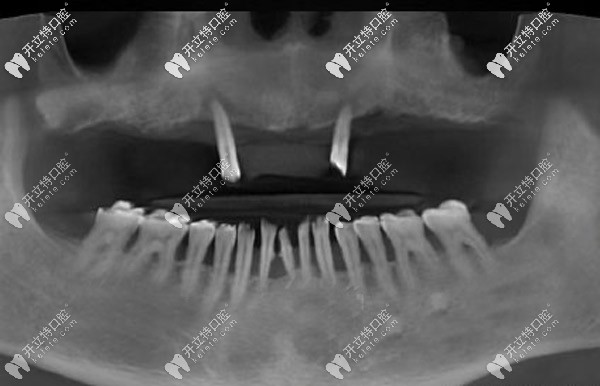

經過口腔CT三維拍片確診,周老先生患有牙周炎,且有牙齦萎縮的情況。羅緣口腔的種植醫(yī)生通過數(shù)字化動態(tài)導航系統(tǒng)在計算機上重建口腔頜骨三維立體模型。

與周老先生進行溝通后,確定了種植體嵌入位置、數(shù)量、種植深度、植體傾斜角度等等,并采用上頜6顆即刻種植技術,運用“數(shù)字化動態(tài)導航種植”方案。